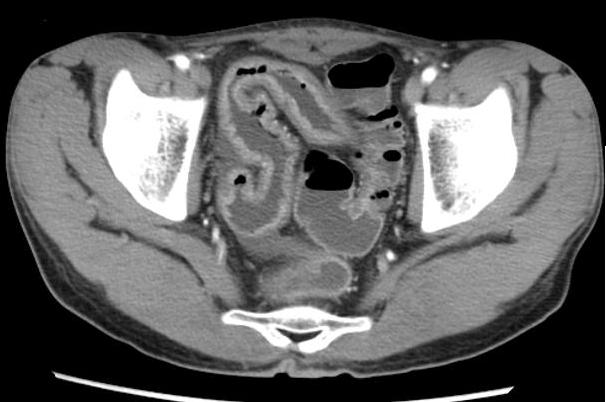

Maladie de Crohn du rectum .

Image epassisement du rectum avec infiltration de la

graisse entre la couche sousmuqueuse et la

couche muscculaire . Ce qui forme en

signe de halo " fat halo sign " |